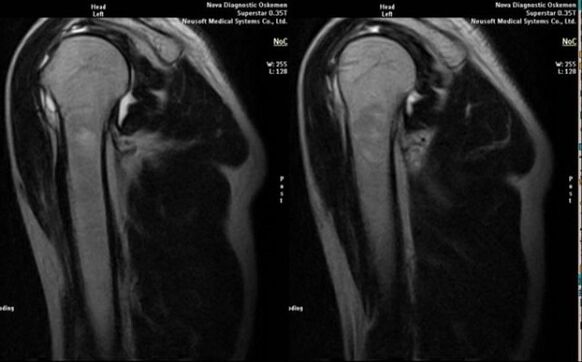

- magnetic resonance imaging and computed tomography;

Signs indicating the development of arthrosis directly include the appearance of significant narrowing of the joint space, sclerosis of the subcartilaginous structures, thinning of the chondrocyte layer itself, the appearance of osteophytes and the deposition of salt crystals in the intra-articular fluid.